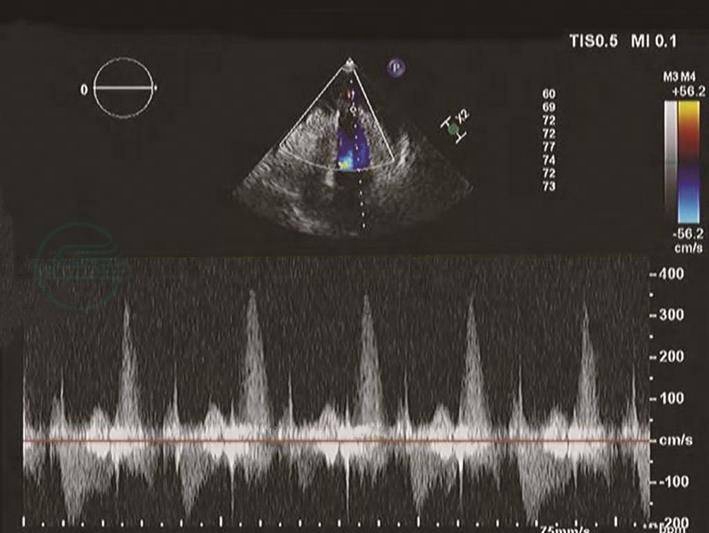

图8心肌梗死后左心室游离壁破裂破口处频谱多普勒声像图

连续波频谱多普勒显示收缩期左心室心尖部破口破入心包腔内的高速血流信号。